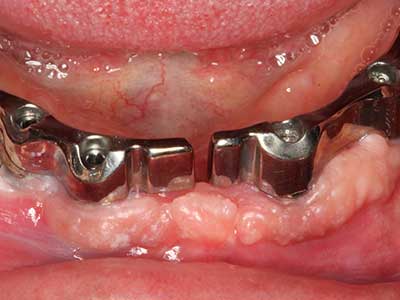

En pacientes de edad avanzada, las enfermedades periodontales marginales representan la razón principal por la que es preciso realizar una extracción. Estas enfermedades tienen principalmente su causa en una colonización bacteriana de la bolsa periodontal y en la inflamación que esta provoca, lo que da lugar a una pérdida del ligamento periodontal. La formación de biopelículas y concreciones subgingivales representa un factor etiológico decisivo para la degradación ósea marginal, por lo que su eliminación cobra una importancia especial en la terapia (Drisko 2014, Plessas 2014).

En el tratamiento de una periodontitis se hace una diferenciación entre la fase inicial y la fase quirúrgica. Además de la instrucción y la motivación entorno a la higiene bucal, en ambas fases debe realizarse una limpieza apropiada de la superficie radicular; a este respecto, en el tratamiento regenerador se elige casi siempre un acceso abierto. La superficie radicular también puede limpiarse mediante piezocirugía utilizando piezas especiales, pues el uso de insertos de diferentes curvaturas permite llegar a zonas de difícil acceso, como son las furcaciones. En esta técnica, la refrigeración interna de agua del sistema ayuda a retirar las concreciones y las bacterias disueltas de la bolsa periodontal. Por otro lado, para reducir a un mínimo la eliminación de la sustancia dental dura, en los sistemas especiales como el Piezomed se ha incorporado una aplicación con retroalimentación. En este caso, según se ejerza más presión sobre la pieza periodontal, la potencia de eliminación se reduce.